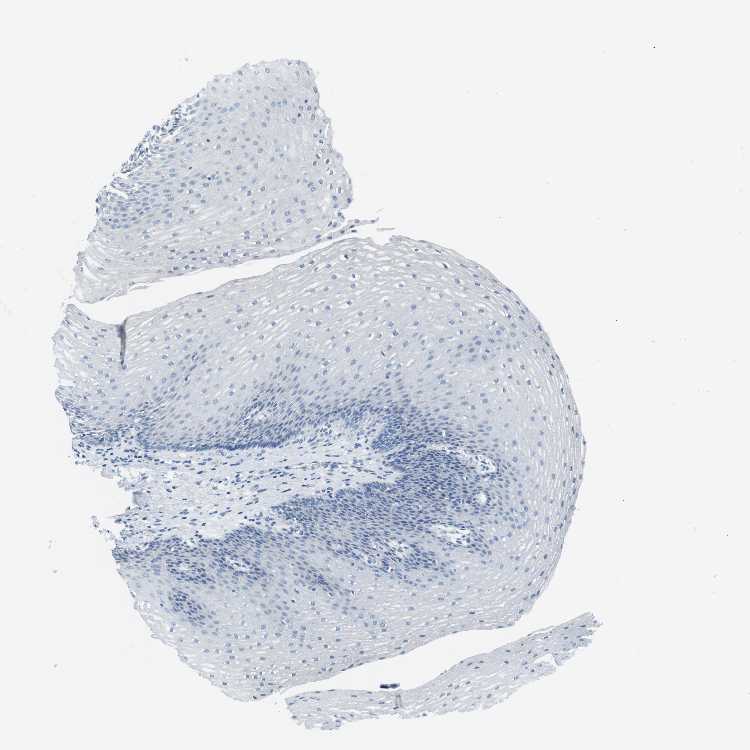

Antibody CAB016275

Squamous epithelial cells Not detected